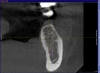

vvshleiko Опубликовано 11 сентября, 2013 Поделиться Опубликовано 11 сентября, 2013 Добрый день. меня мучает вопрос. Все в основном работают без шаблона, а нижняя челюсть практически всегда имеет анатомически орально-букальный наклон. При формировании ложа необходимо соблюдать угол наклона ниж.чел. обычно он порядка 15 градусов. (рис.1). Вот пример когда не учитывается наклон (рис.2) Часто встречаю на КТ работы с таким позиционированием импланта рис.3,4. Коллеги, поделитель советом. Как учитывать этот наклон при формировании ложа? Ссылка на комментарий

Владмир Опубликовано 12 сентября, 2013 Поделиться Опубликовано 12 сентября, 2013 Добрый день. меня мучает вопрос. Все в основном работают без шаблона, а нижняя челюсть практически всегда имеет анатомически орально-букальный наклон. При формировании ложа необходимо соблюдать угол наклона ниж.чел. обычно он порядка 15 градусов. (рис.1). Вот пример когда не учитывается наклон (рис.2) Часто встречаю на КТ работы с таким позиционированием импланта рис.3,4. Коллеги, поделитель советом. Как учитывать этот наклон при формировании ложа? убавтье скорость на деспенсере до 500 и докупите промежуточне фрезы в набор для обеспечения плавности остеотоми, сразу увеличиться тактильное восприятие, 1 1 Ссылка на комментарий